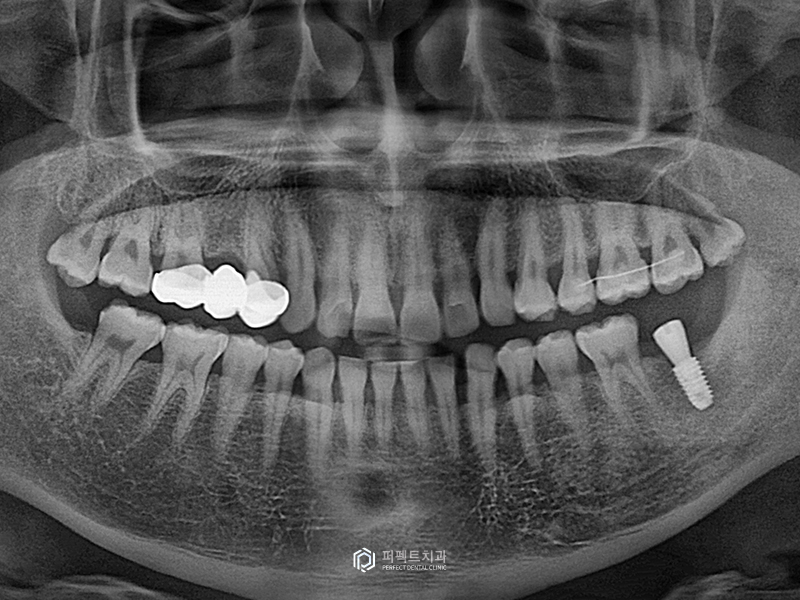

위 환자분의 경우 플랩 리스 수술(Flapless Surgery)로 실로 꼬매지 않는 방법으로 식립을 하였고, 깊이와 위치 모두 잘 식립이 되었습니다.

이런 케이스의 경우 나중에 실을 푸르는 과정이 없어서 환자 분들도 편안해 하시고, 실제로 네비게이션 가이드를 이용한 수술 이상으로 좋은 결과가 나오게 되었습니다.

이처럼 식립 경험이 많거나 기술적인 노하우가 있는 경우라면 네비게이션 가이드에 의존하지 않아도 빠른 시간내에 해결 할 수 있습니다.